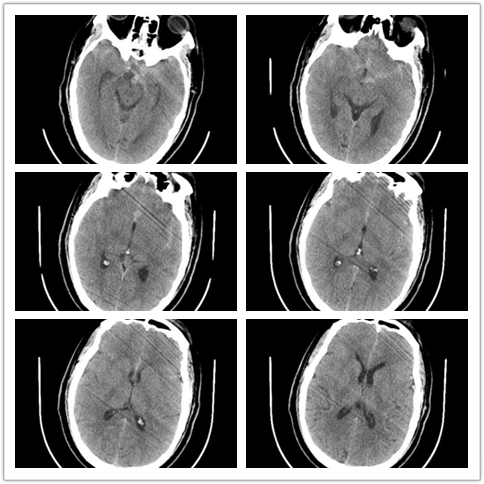

辅助检查

初步诊断:前交通动脉瘤破裂伴蛛网膜下腔出血,低血钾症。